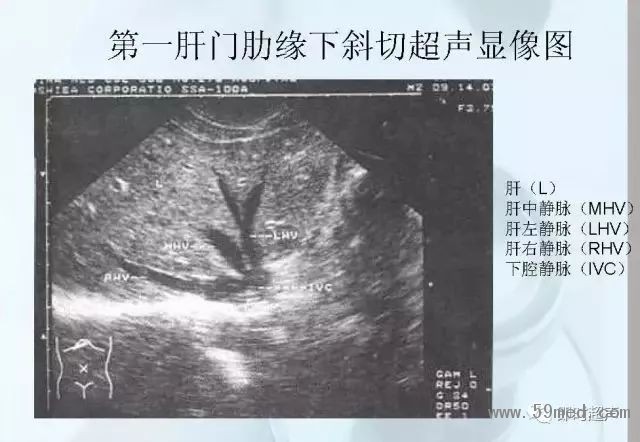

新聞中心 收藏!正常B超解剖圖譜,超實用!